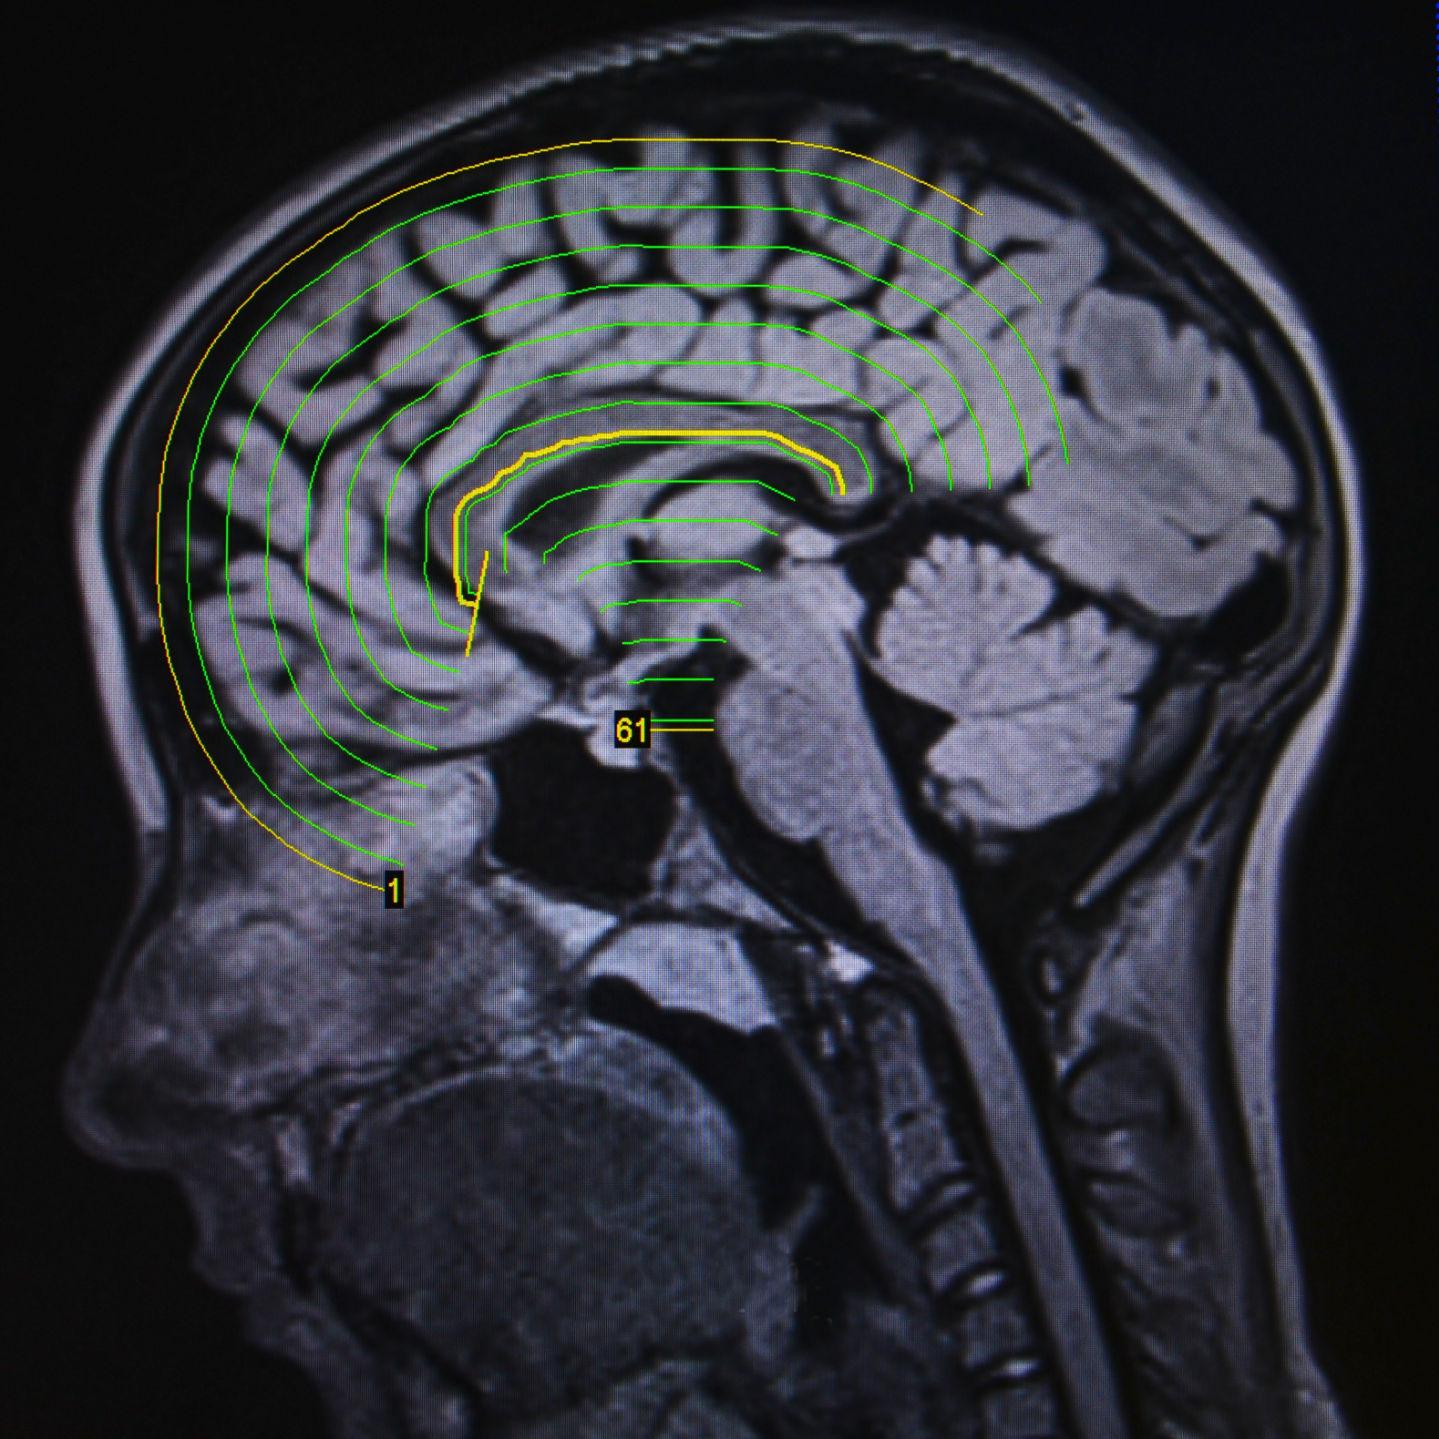

In 1997 a Pokémon episode that aired in Japan sent roughly 700 people mostly children to the emergency room suffering nausea headaches vomiting and epileptic seizuresThe culprit turned out to be light specifically red and blue flashing lights during a battle scene in the episode. Photosensitive epilepsy is not common but it may be diagnosed when you have an EEG test.

How do strobe lights cause seizures. But most of us even the Twitter trolls dont know why such flashes of light affect the brain. Photosensitive epilepsy PSE is a form of epilepsy in which seizures are triggered by visual stimuli that form patterns in time or space.

Certain patterns of light flashing bright lights at particular frequencies synchronize cells within the visual cortex. Whateverwhoever you hold dear shall be blessed if you are a child of God. Find out the incredible facts behind what really causes seizures right now.